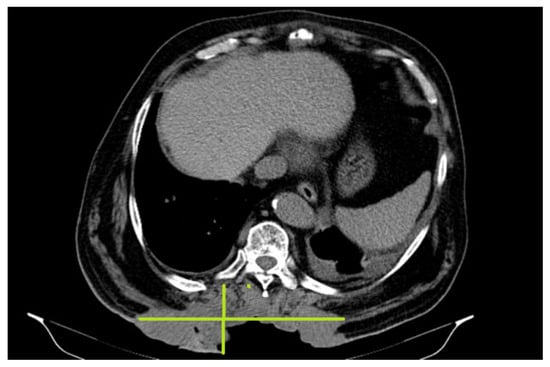

In October 2018, a thoracic abdominal–pelvic CT scan was performed with contrast material. The imaging aspect was aggravated from the previous examination (July 2018) by the significant dimensional progression of the mass, with the malignant tumor’s CT aspect centered at the level of the muscular soft parts corresponding to the posterior thoracic lumbar region (level T7-D2), with invasion of the tegument, subcutaneous fat, and embedding of the spinal processes of the T9–T11 vertebral bodies, axial diameters (197/46 mm), and cranio-caudal diameter (212 mm–11/46 anterior). The presence of central necrotic areas at the level of the tumor mass was also described (Figure 3).

Figure 3. Malignant tumor CT aspect centered at the level of the muscular soft parts corresponding to the posterior thoracic lumbar region (level T7-D2), currently with invasion of the tegument, subcutaneous fat and embedding of the spinal processes.